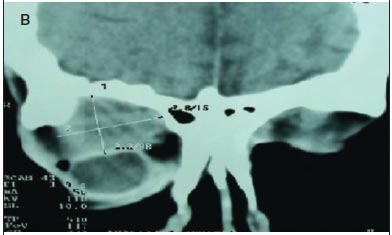

Regarding the malignant neoplasias (seven patients, 58.3%), there were four cases of adenoid cystic carcinoma. The mean age of the patients with adenoid cystic carcinoma was 51 years-old (range, 26 to 65 years-old). Two patients presented a painful palpable mass of rapid growth, proptosis and inferomedial displacement of the globe, and two presented reduced visual acuity, choroidal folds, restricted ocular motility and swelling. Two patients were treated with lateral orbitotomy with resection of the tumor and postoperative radiation, and two were treated with orbital exenteration and postoperative radiation. In these patients, the orbital exenteration and the postoperative radiation were chosen because the preoperative axial and coronal computed tomography showed diffuse orbital involvement, including extraocular muscles and optic nerve. Macroscopically, the tumor was rounded and irregular (Figure 1B). Histologically, two cases were of cribriform pattern (Figure 2C), and two were of solid growth pattern (Figure 2D). One case with cribriform pattern and two cases with solid growth pattern showed necrosis and perineural invasion. The other case with cribriform pattern presented no necrosis and perineural invasion. According to the UICC/TNM Classification, the two cases of cribriform pattern were classified as T2N0M0, and the two cases of solid growth pattern were classified as T4N0M0. The mean follow-up period was 6.5 years (range, 4 to 10 years). No tumoral recurrence was observed in two patients (adenoid cystic carcinoma with cribriform pattern). The patients with solid growth pattern and T4N0M0 developed metastasis to the brain and died of the disease.

The first patient with mucoepidermoid carcinoma was a 70 year-old man, and the second was a 58 year-old woman. Both patients presented a painful palpable mass, proptosis, displacement of the globe off axis, swelling, reduced visual acuity and choroidal folds. The first patient had infiltration into the maxillary and the ethmoid sinus (Figures 3A, B and C) and was treated with orbital exenteration, maxillectomy, ethmoidectomy, postoperative radiation and postoperative chemotherapy. The second patient was treated with lateral orbitotomy with complete resection of the tumor and postoperative radiation. Macroscopically, the second patient showed a soft and reddish tumor (Figure 1C). Histologically, both cases were low-grade and composed of epidermoid cells with mucus-filled vacuoles embedded in a mucoid background (Figure 2E). The mean follow-up was 3.5 years (range, 2 to 5 years). According to the UICC/TNM Classification, the first case was classified as T4N1M0, and the second case was classified as T3aN0M0. The first patient developed metastasis to the brain and died of the disease. The second patient presented no evidence of recurrence of the disease five years after the initial surgery.